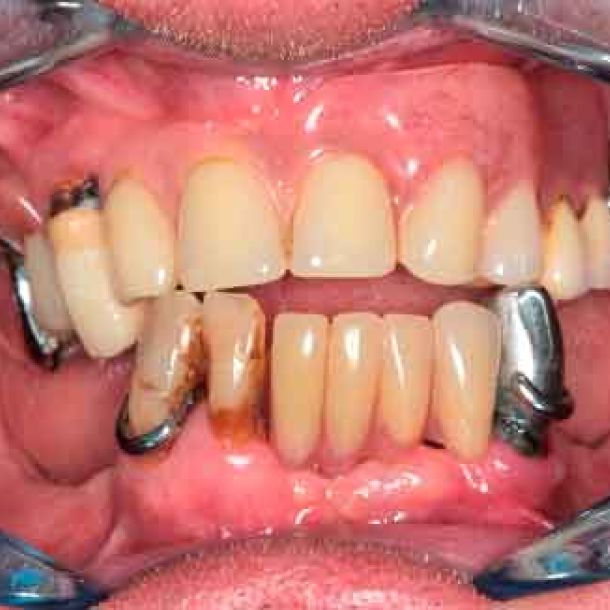

Patient de 66 ans. Souhaite retrouver un confort fonctionnel et améliorer l'esthétique.

Plaintes

- Manque de stabilité de ses prothèses amovibles

- Difficultés à manger

- Affaissement de la lèvre supérieure

Plan de traitement

Les structures parodontales des dents restantes ne sont plus suffisantes. Une édentation est envisagée. Le plan de traitement est orienté vers une prothèse complète maxillaire amovible et une prothèse complète mandibulaire supportée par des implants. Le défi est de passer de la situation initiale aux provisoires en utilisant les données du patient.

Photo - Situation intra-orale